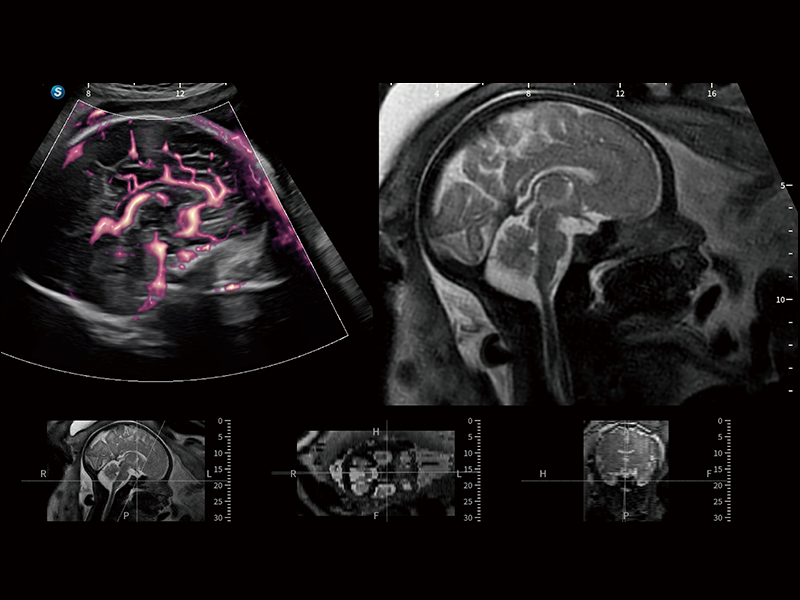

Fine-tuned Hemodynamic Solution

A wide variety of hemodynamic diagnostic techniques enable effective blood flow signal detection across different scenarios.

• FHR

FHR enables the observation of microvascular structure within organs with enhanced sensitivity and improved resolution, ensuring the precision in representing the actual state of blood circulation.

• Micro F

Micro F efficiently distinguishes subtle blood flow signals from overlaying tissue motion, enabling heightened sensitivity and spatial resolution in hemodynamic depiction.

FreeFusion